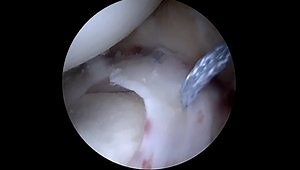

Part 1: Foundations of Biointegrative Collagen in Orthop

An Innovative Biointegrative Collagen Solution for Orthopedic